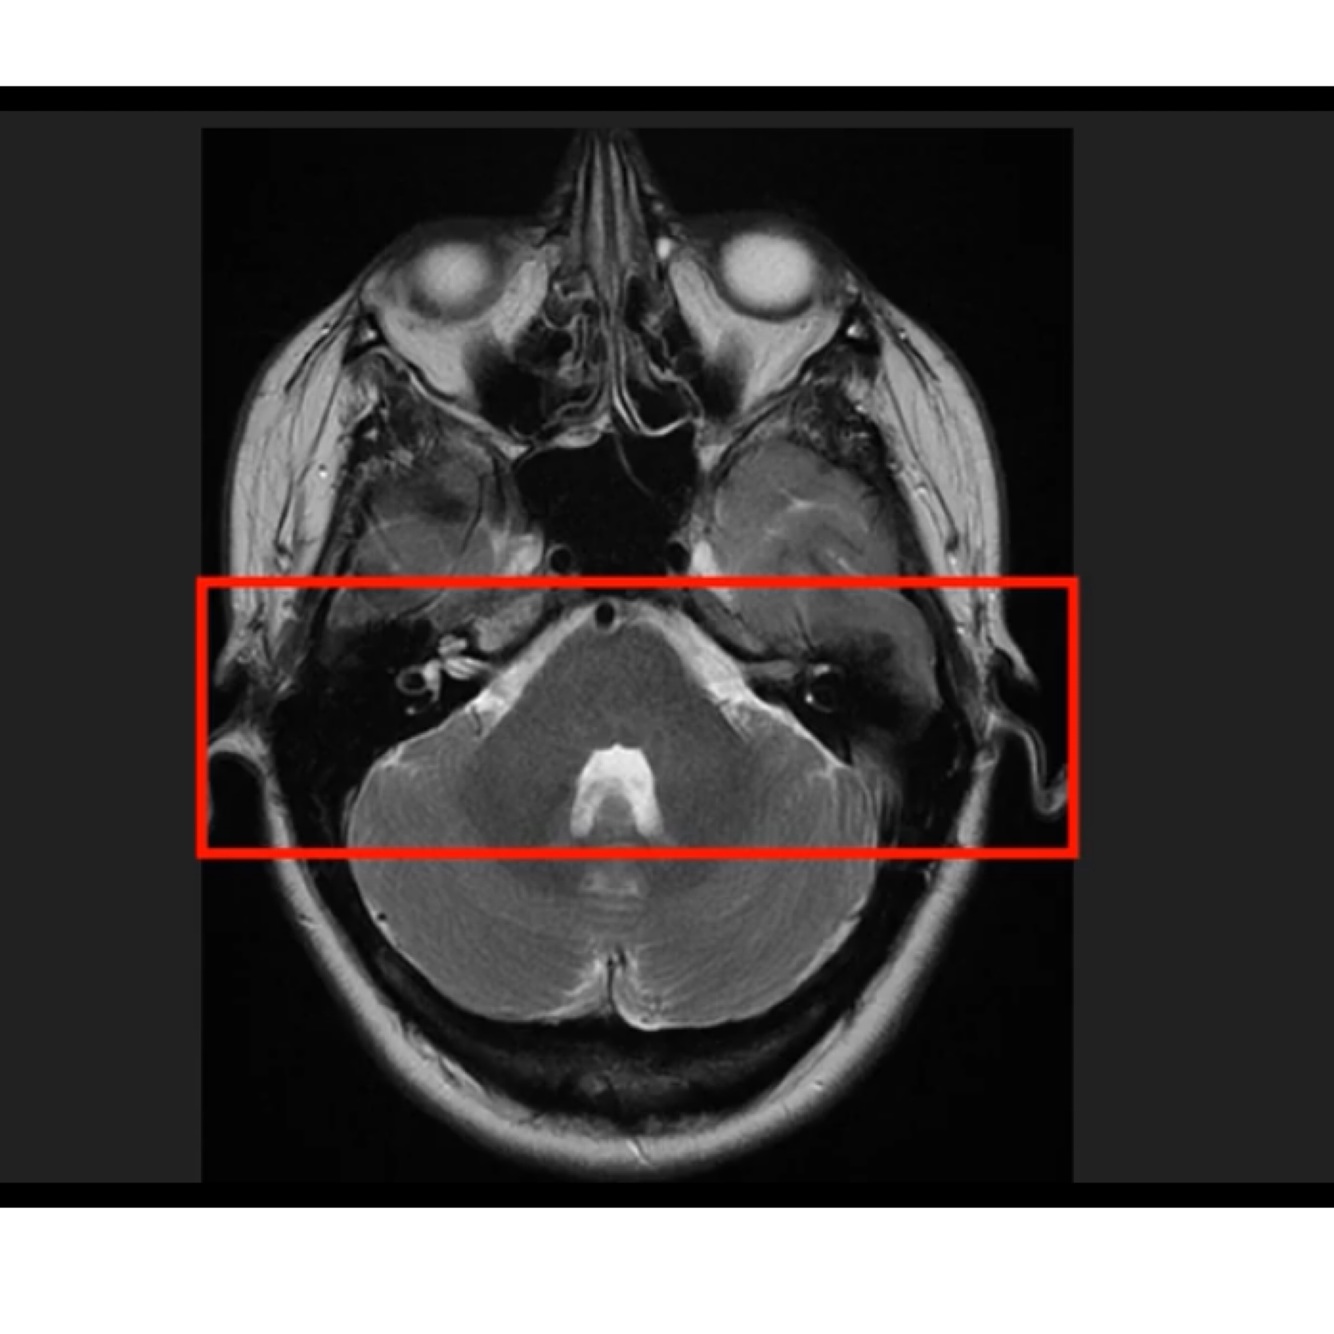

Structures surrounding the brainstem and inner ear?